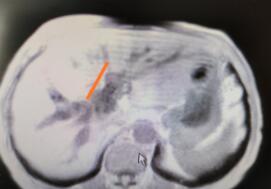

患者是一位71岁的老人,半个月前出现皮肤瘙痒,全身皮肤黄染,从当地一家医院转诊湘雅二医院肝脏外科。接诊后,戴卫东教授团队为患者进行检查后,确诊为Bismurth IV型肝门胆管癌。

肝门部胆管癌手术涉及到肝叶切除及胆管重建,必要时还需要修补或重建大血管,为肝胆外科难度最高的手术之一。常规手术需要在腹部打开约20厘米的切口,术后容易并发胆漏及出血,一般需要12天才能出院。根据患者年龄和身体条件,并经过充分术前准备及详细论证后,专家团队最终建议患者行达芬奇机器人辅助下肝门部胆管癌根治术。

与传统手术相比,机器人手术仅需4个1厘米的小切口,所有的手术操作均依靠机械手完成。随着戴卫东教授的操纵,机器手臂灵巧、精准地实施操作,完整切除肝门部肿瘤,残余胆管远端均达到R0切除(无癌残留)。“高度放大的3D手术视野几乎无任何死角,可以更加清晰地暴露肝门淋巴及神经结缔,便于肝门部淋巴及神经结缔组织彻底清扫。完整切除肝门部肿瘤后,再行左肝管空肠内引流及右肝管、尾叶胆管围肝门空肠吻合,吻合方便、严密,极大地减少了术后胆漏的发生率,同时,最大程度上避免了对正常肠管的损伤。”戴卫东介绍,手术历时4小时,术中出血仅100ml,术后第2天患者开始进食,黄疸逐步下降,并于术后第5天顺利出院。